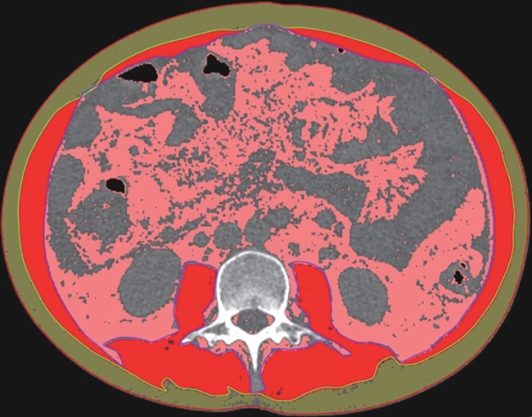

基于CT图像的腹部肌肉内部分层分析对原位肝移植术后并发症的预测价值

石鑫, 梁重霄, 张蓓, 王继萍

2025, 41(2): 314-321. DOI: 10.12449/JCH250218

摘要(706) HTML (336) PDF (3265KB)(40)

摘要:

目的  本文旨在肌肉脂肪浸润的基础上,利用分层分析的方法将肌肉内部按照不同的密度范围划分成不同的亚分区,进一步研究肌肉密度改变对原位肝移植术(OLT)后并发症(Clavien-Dindo≥Ⅲ)的影响。  方法  回顾性分析2013年5月—2020年9月于吉林大学第一医院行OLT的145例患者,以患者腰3椎体水平最大层面的CT平扫图像作为原始数据,利用Neusoft Fatanalysis软件对图像进行相关肌肉参数的测量。符合正态分布的计量资料组间比较采用成组t检验;不符合正态分布的组间比较采用Mann-Whitney U秩和检验。计数资料组间比较采用χ2或Fisher检验。利用RIAS软件进行临床特征提取及分析建模,分别建立逻辑回归(LR)、支持向量机(SVM)、随机森林(RFC)3种机器学习模型,并绘制不同模型的受试者操作特征曲线(ROC曲线)、校正曲线、决策分析曲线,计算ROC曲线下面积(AUC)、灵敏度、特异度、精确率、F1分数、准确率。  结果  采用肌肉分层分析前的7种临床特征建立LR-C、SVM-C、RFC-C 3种机器学习模型,其中RFC-C模型测试集的AUC值为0.803、灵敏度0.588,特异度0.778。采用肌肉分层分析后的16种临床特征建立的LR-CS、SVM-CS、RFC-CS模型中,LR-CS及SVM-CS模型测试集的AUC值较高,均为0.852,灵敏度分别为0.765、0.706,特异度分别为0.889、0.926,通过对比肌肉分层分析前后各模型测试集的AUC、灵敏度、特异度、精确率、F1分数、准确率后发现,肌肉分层分析后预测模型的参数均有所提升。通过对比各预测模型的决策分析曲线和校正曲线,发现LR-CS及SVM-CS模型对于预测OLT患者术后并发症(Clavien-Dindo≥Ⅲ)具有良好效能。  结论  在肌肉脂肪浸润的基础上,利用分层分析的方法将肌肉内部按照不同的密度划分成不同子区,对于OLT患者术后并发症有一定预测价值。